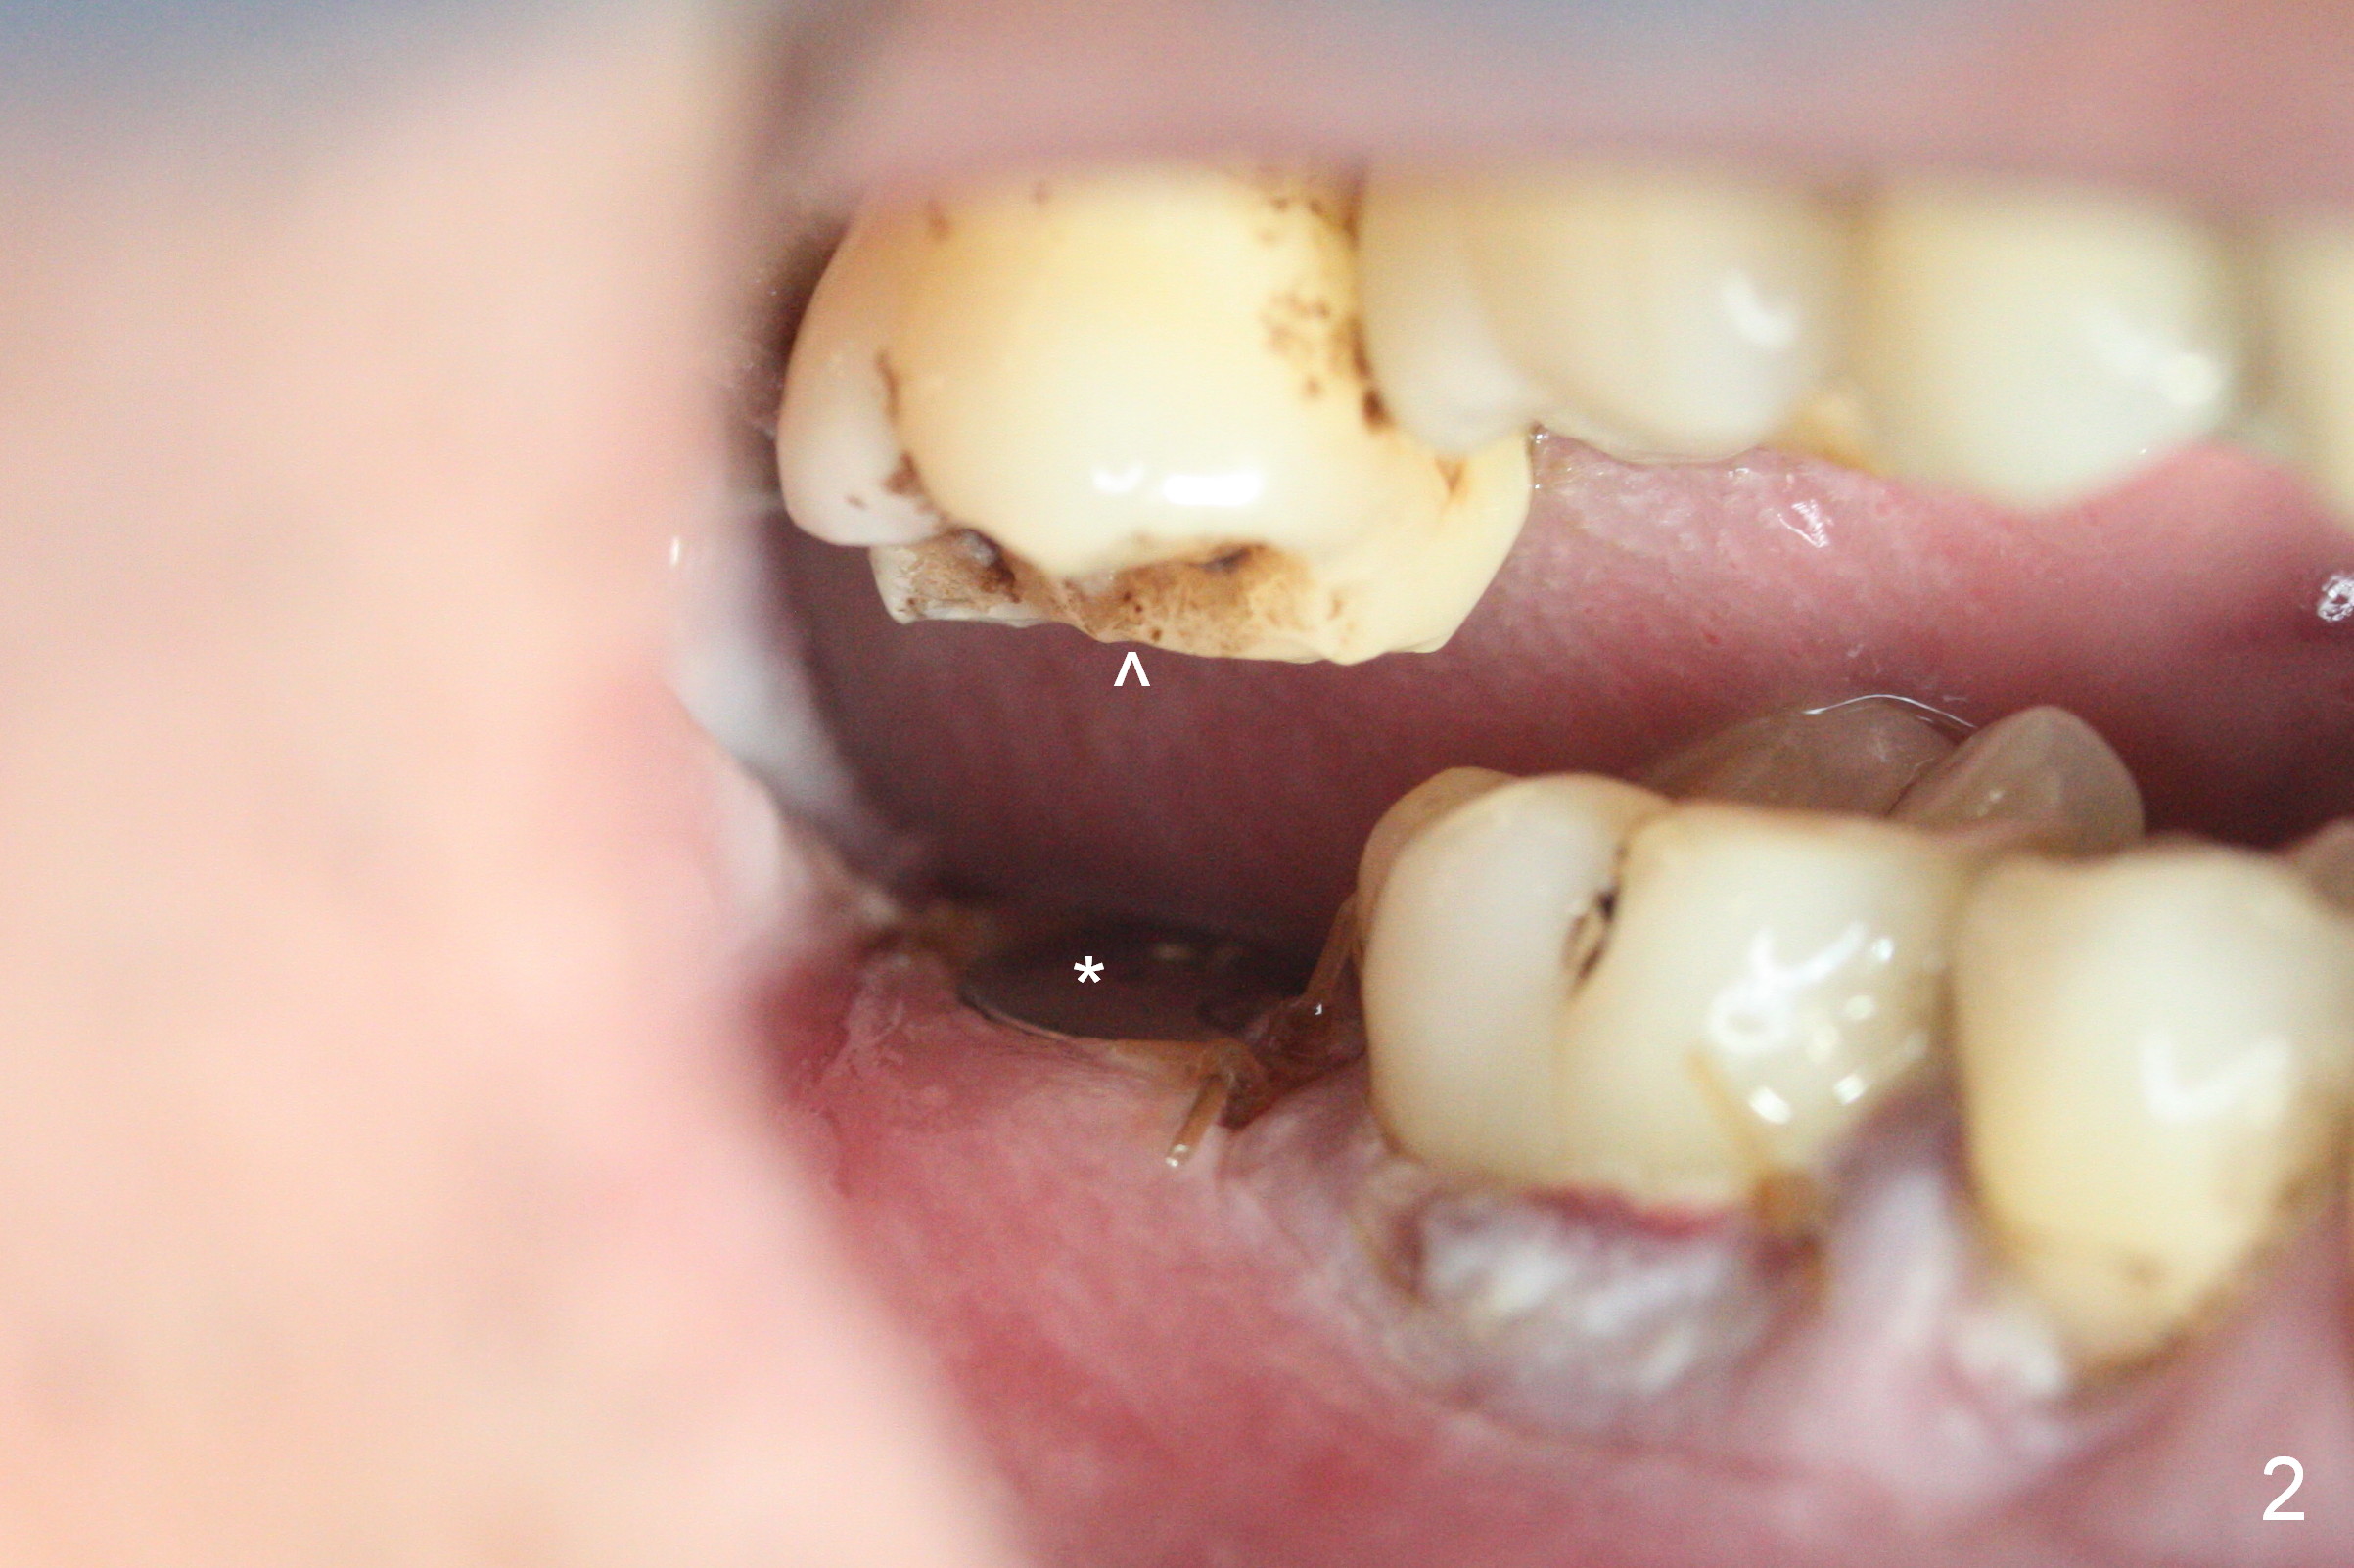

Two days post #31 implant placement, the patient returns for orthodontic intrusion of the tooth #2 with mini-implants (Fig.1). The palatal cusps have been trimmed (Fig.2 ^), since they almost contact a healing abutment at #31(*, Fig.3). Two mini-implants are to be placed mesiobuccal and distopalatal to the affected tooth. After minimal injection of Lidocaine, a 1.6x6 mm Tomas implant is placed in full length mesially (Fig.4), while the other (1.6x8 mm) half way (Fig.4). Following change in implant site mesially (Fig.6 >), the implant is half inserted (Fig.5). It appears that the tip of the distal implant is toward the tooth #1 (Fig.5). After withdrawing the implant partially, it is re-directed to apparently ideal trajectory (Fig.7). Ideally the mesial implant (Fig.8) should have been placed partially initially (Fig.4,5,7) so that the trajectory could have been able to be changed.